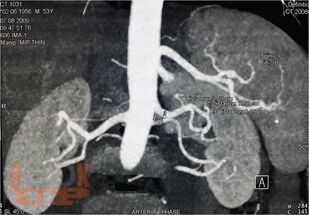

В пособии изложены вопросы отбора пациентов, предоперационной подготовки и техники лапароскопической донорской нефрэктомии при проведении трансплантации почки от живого родственного донора пациентам с терминальной стадией хронической почечной недостаточностью.